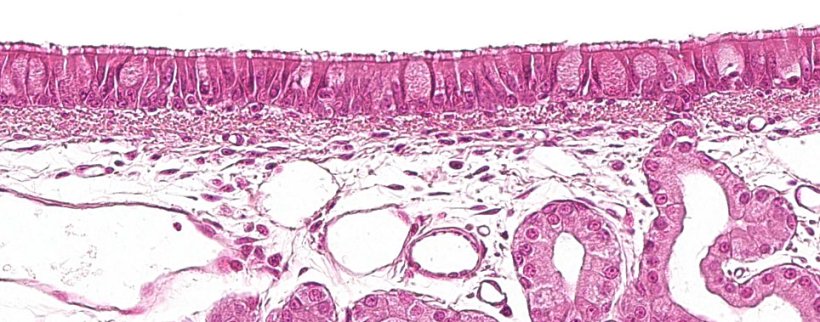

Pierwsza część układu oddechowego, strefa przewodząca lub strefa oddechowa, biegnie od jamy nosowej do ostatnich gałęzi oskrzeli, a także obejmuje zatoki nosowe i przynosowe, które są połączone z jamą nosową, nosogardzielą i krtanią. Wszystkie te struktury rurowe są wyściełane nabłonkiem wielorzędowym urzęsionym z komórkami kubkowymi (ryc. 1), który jest odpowiedzialny za jeden z głównych układów obronnych błony śluzowej dróg oddechowych - układ śluzowo-rzęskowy. Ten system składa się z rzęsek komórek nabłonka oddechowego, wraz z wydzielinami z komórek kubkowych i gruczołów śluzowo- surowiczych, znajdujących się pod błonś śluzoweą dróg oddechowych. Ich główną funkcją jest eliminacja cząstek, które dostają się z wdychanym powietrzem. Gruczoły wydzielają przezroczystą, bogatą w białko ciecz między rzęski, tworząc medium, które ułatwia ruch rzęsek w górę. Śluz wydzielany przez komórki kubkowe osadza się na rzęskach i umożliwia przywieranie do nich wdychanych cząstek. Ruch rzęsek w górę popycha śluz w kierunku górnych dróg oddechowych. Śluz może być następnie połknięty i przedostać się do przewodu pokarmowego, gdzie jest trawiony, lub może być wydalony przez usta i / lub jamę nosową. Bakterie takie jak Mycoplasma hyopneumoniae, która powoduje utratę rzęsek, lub wirusy, takie jak grypa świń lub koronawirus oddechowy, które powodują zniszczenie komórek nabłonkowych, działają patogennie, niszcząc ten system obronny.

Ryc. 1: Nabłonek wielorzędowy urzęsiony z komórkami kubkowymi, charakterystyczny dla układu oddechowego.